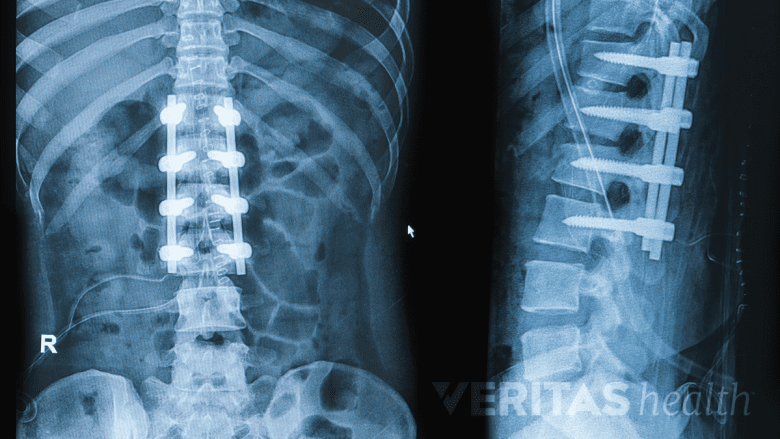

Robot-assisted surgeries may reduce the risks associated with pedicle screws and rods.

A highly controlled surgical approach is possible with robotic assistance, which may help in the more accurate placement of spinal instrumentation, such as pedicle screws, lowering the rate of complications associated with the placement of such instrumentation in the spine.

However, there is inconclusive research on the effectiveness of these surgeries. Some studies have stated reduced complications by approximately 48% when comparing robot-assisted spine surgeries to traditional surgeries, while others have reported higher rates of complications in certain types of robot-assisted surgeries, such as lumbar fusion surgery.